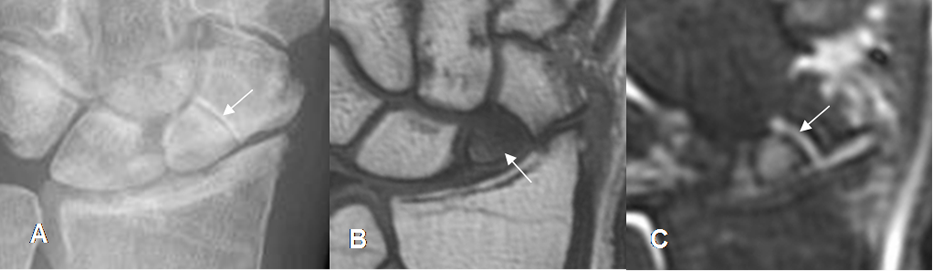

Fig 48. Fractura del escafoides.

A: Rx AP. Fractura transversa del escafoides, en su tercio medio.

B: RM sagital en T1. La fractura se identifica, como línea hipointensa.

C: RM coronal en STIR. Edema y fractura del escafoides (Flecha delgada). Adicionalmente se aprecia contusión del semilunar (Flecha gruesa).